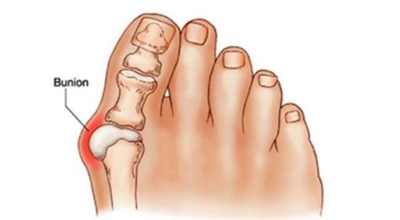

무지외반증 증상

육안상으로 확연하게 엄지발가락 과 같은 변형 보이며 초기에는 굳은살도 관찰되고 약간의 통증도 있습니다. 엄지발가락 돌출 부위의 통증으로 이 부위가 신발에 자극을 받아 두꺼워지고 염증이 생겨 통증이 발생합니다. 휘어지지 않은 발바닥에 굳은살로 인해 정상 보행이 어렵고 심한 경우 통증으로 인하여 신발 착용은 물론 정상 보행도 어려워집니다. 연속적으로 증상이 악화되면 엄지발가락이 겹쳐지거나 탈구 될 수도 있습니다.

엄지발가락이 옆으로 휘어 관절에 비정상적인 힘이 가해져 퇴행성 관절염이 생길 수 있죠. 그리고 엄지발가락이 지지해야 할 발바닥 압력이 2, 3번째 발가락으로 옮겨지면서 발바닥 쪽에 굳은살이 발생할 수 있고 발가락 뼈 사이의 신경이 붓고 통증이 나타나는 지간신경종이 합병될 수도 있습니다.